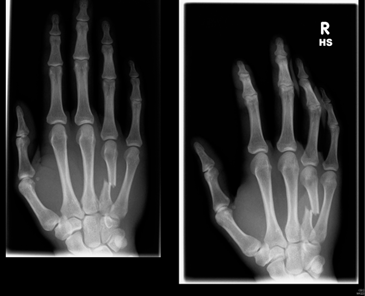

Mr Brown, a 23 year old from Manchester fell while on holiday in France. He was skiing at the time, and fell, fracturing his hand. He wanted to know whether he required to have an operation in France, or whether he could wait until he returned home. The cost for this report was an additional £250.

Mr Brown registered as a user of the eCare Portal which is separate to this website. He uploaded a photo of his scans as part of the info he provided when he registered his case initially.